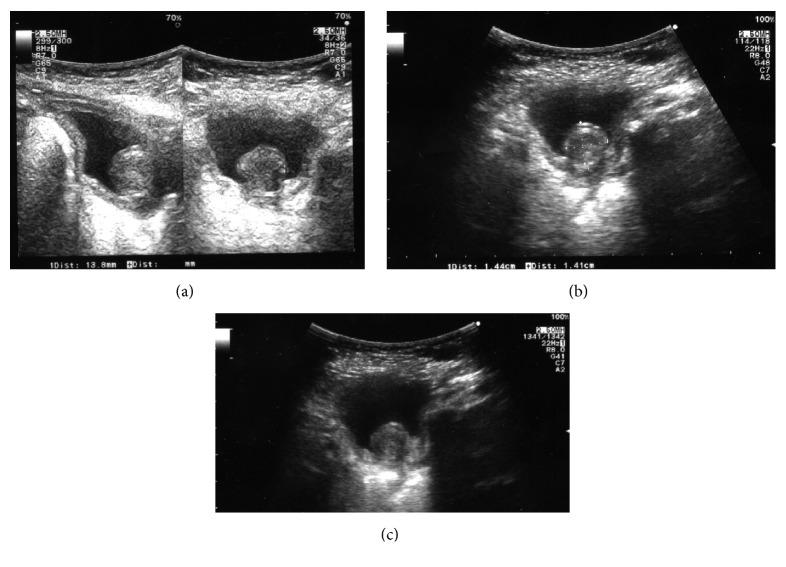

Visceral solitary myofibromas are uncommon in childhood. We report a case of a solitary asymptomatic visceral myofibroma of the bladder trigone occurring in a 3-month-old boy. Once malignancies were ruled out by cystoscopy, radical excision was performed in order to avoid any potential impairment of bladder dynamic. Postoperative course was uneventful and patient was discharged on day 3 after surgery. After 36 months of follow-up, the patient is toilet-trained and remains well; bladder function is normal.